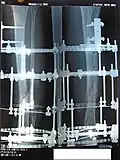

Процедура лечения открытого перелома большой и малой берцовой костей аппаратом Илизарова. Фотографии и рентгенограммы одного и того же пациента в течение курса лечения. Снимки 2 — 6 сделаны через четыре недели после перелома (две недели после наложения аппарата).

Рентгенограмма перелома и первоначальный внешний фиксатор, наложенный в течение 24 часов после поступления в больницу. -

Рентгенограмма места перелома сразу после наложения аппарата Илизарова -

Рентгенограмма места перелома (через два месяца после перелома), № 1 -

Рентгенограмма места перелома (через два месяца после перелома), № 2 -

Рентгенограмма места перелома (через три месяца после перелома), № 1. Костная мозоль образуется вокруг места перелома -

Рентгенограмма места перелома (через три месяца после перелома), № 2. Костная мозоль образуется вокруг места перелома -

Рентгенограмма места перелома (через четыре месяца после перелома)